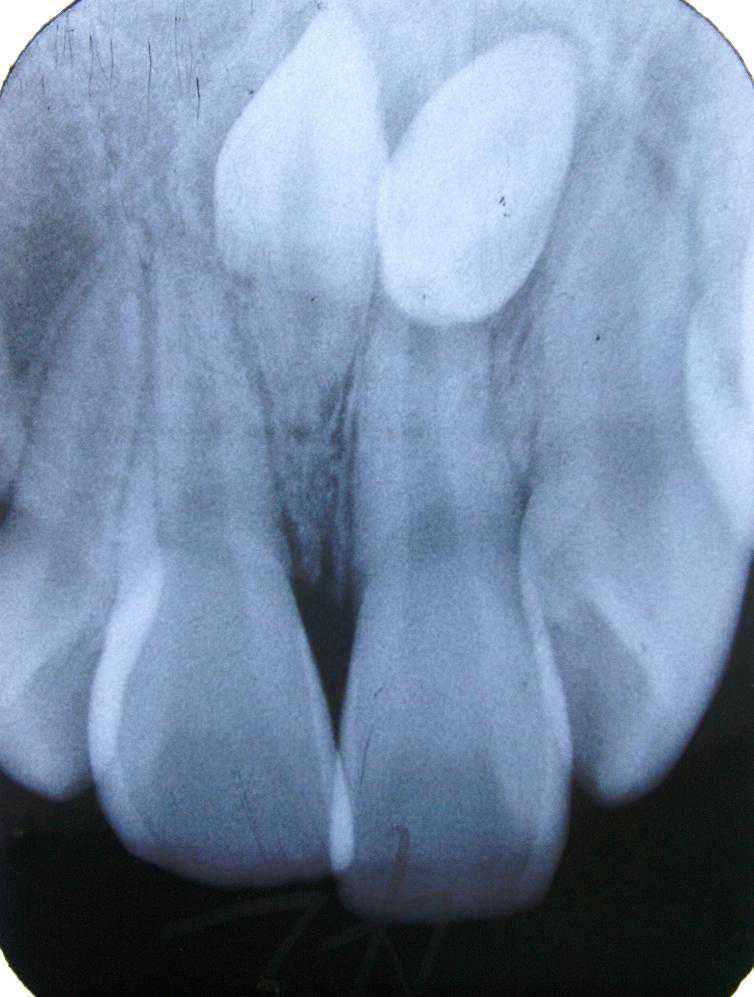

齿我妹妹的上门牙最近总是疼,去医院拍了个牙片,竟然发现在两颗门牙之间还有一颗牙齿。从外表根本看不出来,是在骨头里面埋着的。(图123)

牙有的多生牙先于所在部位恒牙的萌出,故而影响了恒牙的正常萌出和排列,患儿的家长误以为是恒牙萌出,并没有引起重视,待发现时已经错过最佳的治疗时机,拔除多生牙后再配合牙齿矫正才可将牙齿排齐;也有的多生牙和恒牙同时萌出,造成恒牙萌出位置偏斜、牙列拥挤等问题;个别多生牙由于埋伏位置过深或倒置,无法萌出,不易被察觉。(图4)